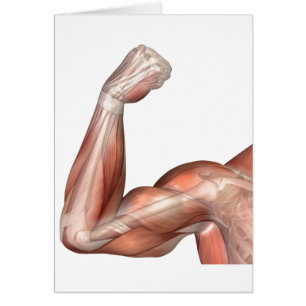

Illustration D'Un Bras Flexé Montrant Des Biceps H

Prix de vente 6,48 $CA. Prix Initial 7,20 $CA.